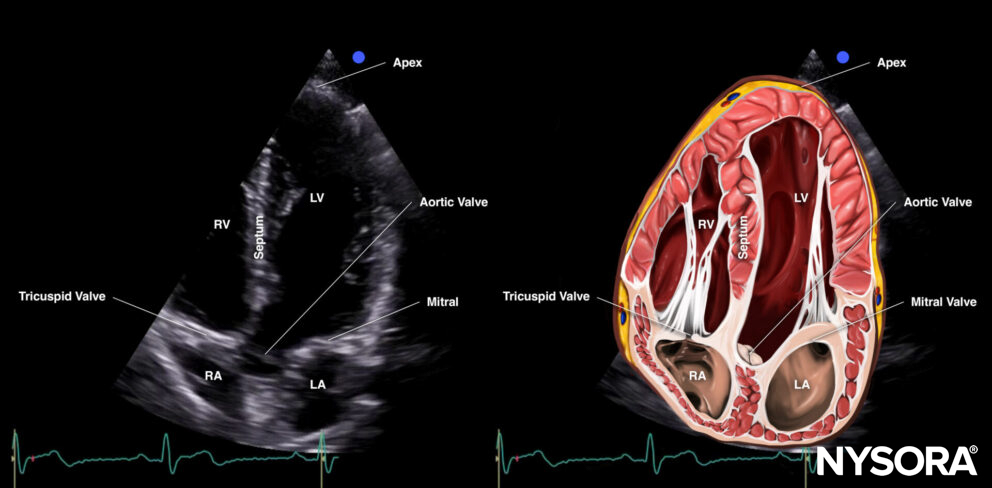

The apical four-chamber view cuts the heart through the coronal plane.

Sonoanatomy of the heart in the apical four-chamber view. Left atrium (LA), left ventricle (LV), right atrium (RA), right ventricle (RV), septum, tricuspid valve, mitral valve, apex.

Reverse ultrasound anatomy:

Reverse Ultrasound Anatomy of the heart in the apical four-chamber view. Left atrium (LA), left ventricle (LV), right atrium (RA), right ventricle (RV), septum, tricuspid valve, mitral valve, apex.

Practical use:

- Left ventricle size and function

- Right ventricle size and function

- Septal kinetics

- Valve function: Doppler